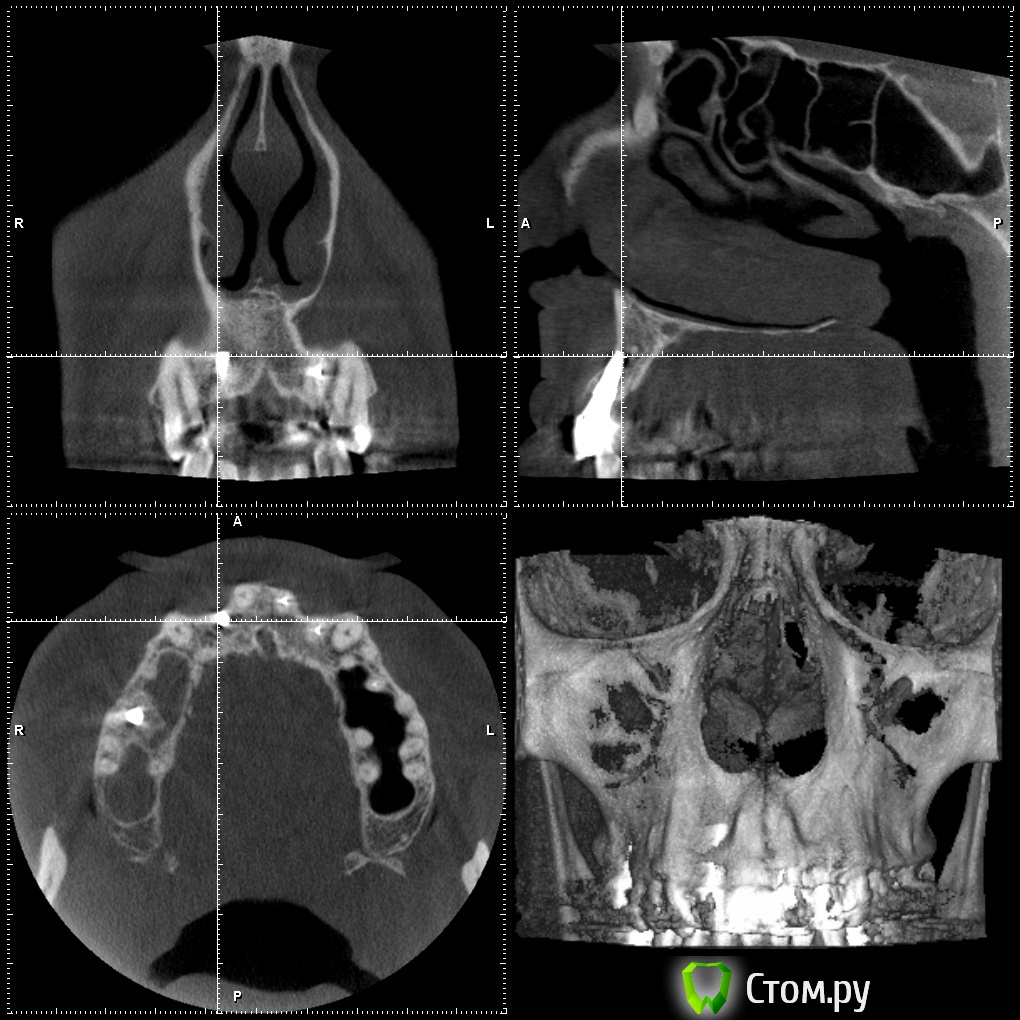

Britanez Опубликовано 2 июня, 2014 Поделиться Опубликовано 2 июня, 2014 В июле 2013 года были установлены 2 импланта 2 и 6 , 6ка с открытым синус лифтингом, в феврале 2014 установили коронки. Две недели назад обратил внимание на воспаление десны над обеими коронками,появился свищ над вторым имплатом и выделения белого цвета.Обратился к врачу, назначили пропить антибиотики 5 дней и сделать КТ. Антибиотики пропил над 6кой воспаление прошло ,над 2кой осталось,по результату КТ сказали что ушла кость и 2ку скорее всего придется удалять.Подскажите что можно сделать в данной ситуации, можно ли сохранить имплант?Ссылка на кт: http://my-files.ru/vbs51uСделал срезы кт: Ссылка на комментарий

Britanez Опубликовано 9 июня, 2014 Автор Поделиться Опубликовано 9 июня, 2014 Извините, что пишу в Вашей теме, просто хочу выразить сочувствие. Напишите потом, пожалуйста, как пойдут Ваши дела дальше, и что говорят врачи, почему произошло отторжение? А синус делали одновременно с постановкой обоих имплантов?? И ещё, выскажу просто мнение для администрации сайта и стоматологов, хотя сообщение наверняка удалят. Меня удивляет, для чего тогда сделана ветка для вопросов пациентов, когда за несколько дней ни один уважаемый стоматолог не заглянул и ничего не написал... После этого задумаешься, стоит ли размещать свои снимки, фотографии и проблемы..... Отвечу здесь если кому то интересно.Синус на 6ку делали одновременно с постановкой двух имплантов.Врачи говорят, что воспаление пошло из-за того что верхний край импланта вышел за пределы костной ткани (на втором снимке видно) и при нагрузке началось воспаление, хотя имплант стоял очень крепко ,открутить не смогли, выпиливали, чем то типа круглой коронки.Если здесь кто нибудь из врачей объяснил (подтвердил) причину воспаления, был бы очень признателен. Ссылка на комментарий

Bier Опубликовано 9 июня, 2014 Поделиться Опубликовано 9 июня, 2014 Имплантат частично стоял не в кости и кости судя по в ему было очень мало еще до имплантации. Ссылка на комментарий